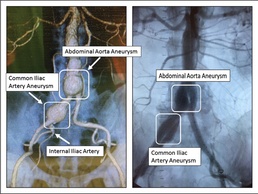

William Beaumont Army Medical Center became the first military treatment facility in the Department of Defense (DoD) to use the first “off-the-shelf” aortic branch device (stent graft) indicated for the endovascular treatment of common iliac artery aneurysms, April 18.

Vascular surgeons at the hospital successfully performed Endovascular iliac artery Aneurysm Repair (EVAR) on a 60-year-old male patient who elected to employ the new stent graft for his surgery.

The aorta is a large artery that carries blood to the abdomen, pelvis and legs. An aortic aneurysm is when part of this artery becomes too large or balloons outward. Common iliac arteries are located just below the abdomen, in the pelvis.

“Any type of aneurysm is when an artery is 1 ½ times the normal size, if it dilates more the rupture rate increases,” said Aidinian, 43, native of Los Angeles. “Most aneurysms are abdominal aneurysms. As many as 20 percent of patients with abdominal aortic aneurysms also have iliac artery aneurysms, which are aneurysms in the pelvis.”